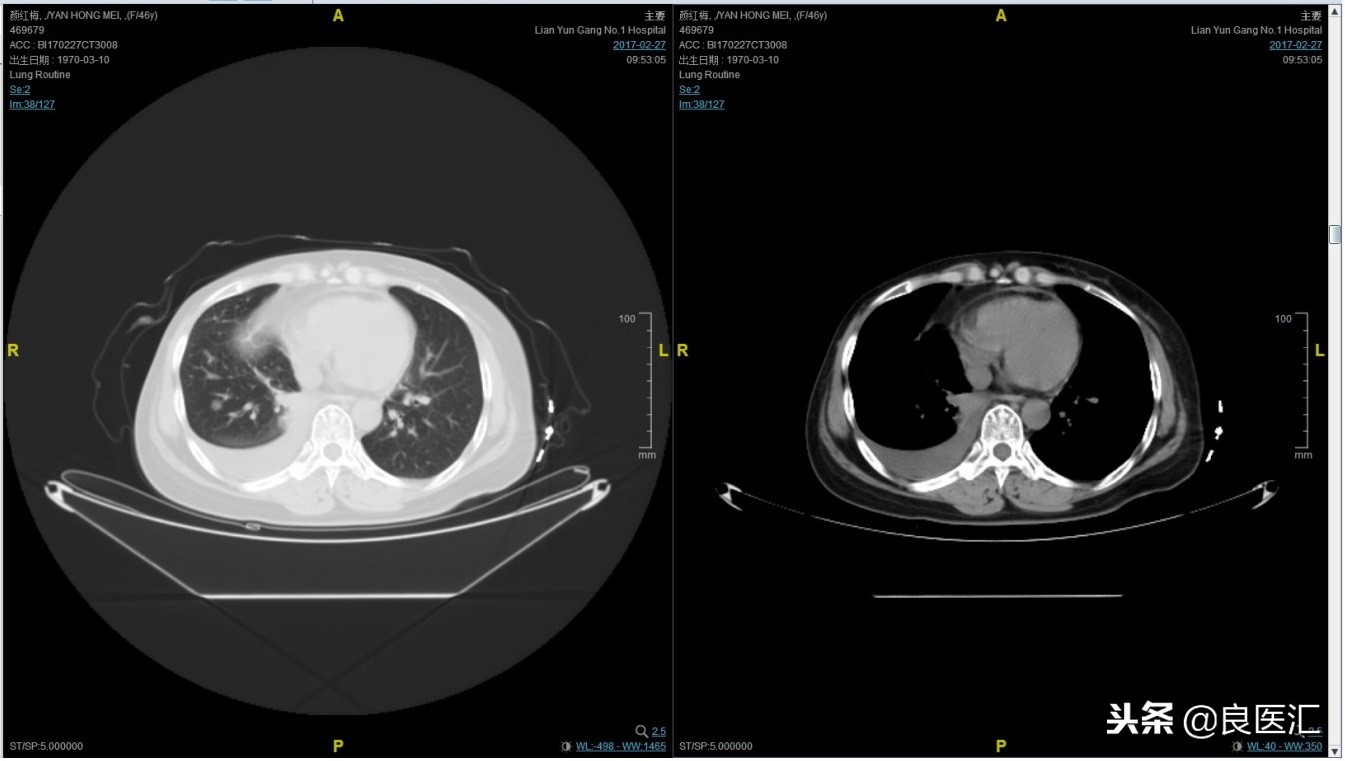

第四次复发

2017-02-27患者因气喘胸闷再次就诊。患者肺部病灶进展,同时出现肝脏转移。再次给予曲妥珠单抗+长春瑞滨化疗一周期,效果不佳,推荐换用TKI治疗,患者放弃治疗。PFS3=12个月。